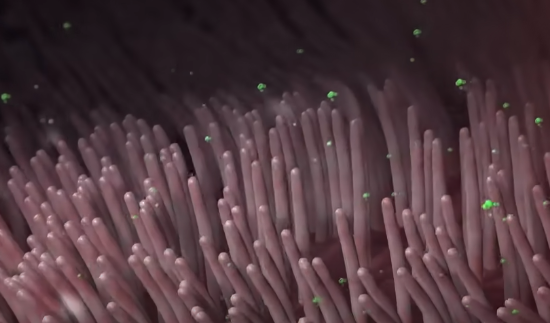

与此同时,病毒会大面积屠杀肺部的纤毛细胞,让它们无法拦截病毒等外部侵略者。